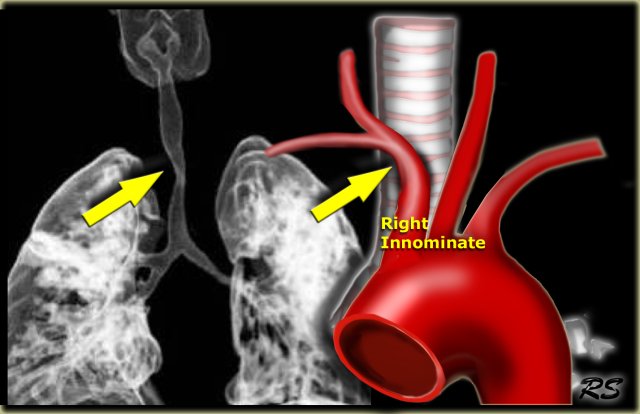

Innominate artery compression syndrome with compression of the trachea Innominate artery compression syndrome with compression of the trachea

Innominate artery compression syndrome

On the left a sagittal scanogram, axial image and sagittal reconstruction of a 5 year old girl with noisy breathing and occasional episodes of cyanosis.

First look at the images then continue.

The findings are:

1. anterior compression of the trachea

2. brachiocephalic (innominate) artery is located more to the left and compresses the trachea

The diagnosis is the innominate artery compression syndrome.

In infants the innominate artery arises more to the left than in adults, so it's got to go in front of the trachea. It may compress the trachea, leading to stridor, cough and dyspnea. This compression decreases with age and these patients will outgrow it.

The compression in the innominate artery compression syndrome is located on the right anterior side and at the level of the thoracic inlet.

This is much higher than in the double arch or Right Aortic Arch with Aberrant left subclavian

On the left another case with mild compression on the trachea.